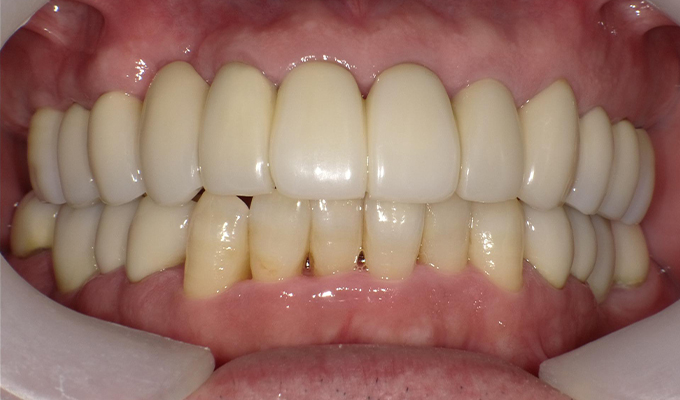

case1インプラントとメタルボンドブリッジの症例

最新メンテナンス時(2024年)

- 初診時の年齢

- 60代女性(2010年)

- 主訴

- ちゃんと咬めるようになりたい。最近孫が生まれたから一緒に歌ったりしたいけど、今は歌うこともできないから・・・・。と

- 治療内容

- 5年ほど前に入れ歯を作ったそうですが合わなかったので使用してなかったせいか前歯がグラグラになっていて今にも抜けそうな状態でした。

保存が難しい歯を抜歯し、上はインプラント8本、下は奥歯にインプラント4本埋入しました。

補綴は変色しないメタルボンドを選択されたので治療完了して11年経過してもとてもきれいな状態で維持されています。

初診時にお話しされていたお孫さんも中学2年生になったそうで、歯の治療をしたおかげで充実した毎日が送れてます、とメンテナンス時もいつも嬉しそうにされています。